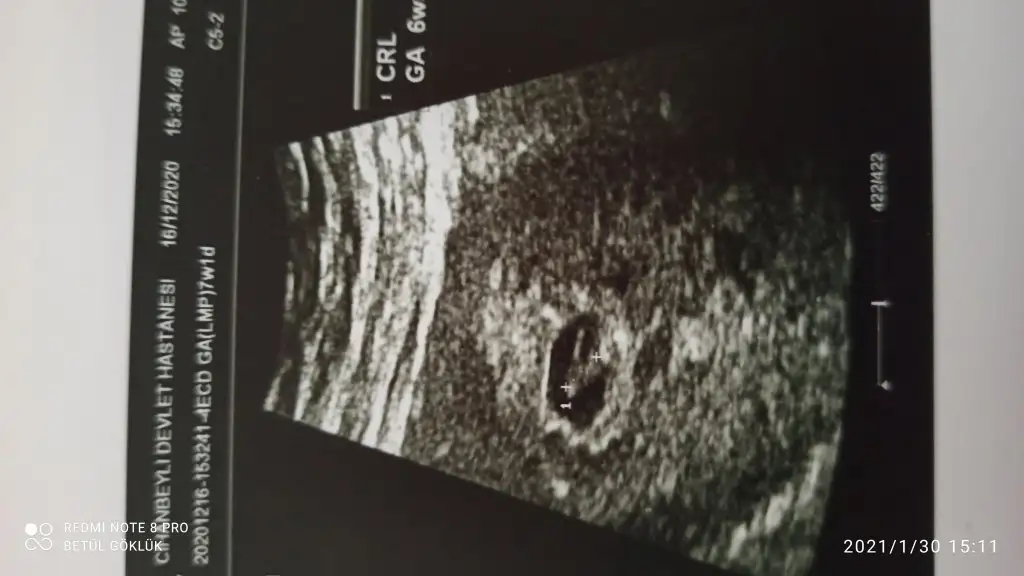

İlk ultrason resimlerinizi paylaşın ramzi teorisine göre cinsiyeti tahmin edeyim bakalım tutacak mı?

6 haftalık. Sizce nedir?